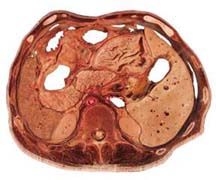

腫塊組織切片可見分化成熟的上皮細胞呈條索狀浸潤性生長,散在分布於疏鬆結締組織中,周圍有大小不一的黏液池,黏液池中有少數排列整齊、分泌亢進上皮細胞的索狀上皮結構儘管所見到的腫瘤為良性,但它能發生局部浸潤和蔓延,而影響周圍的重要結構(圖1)。